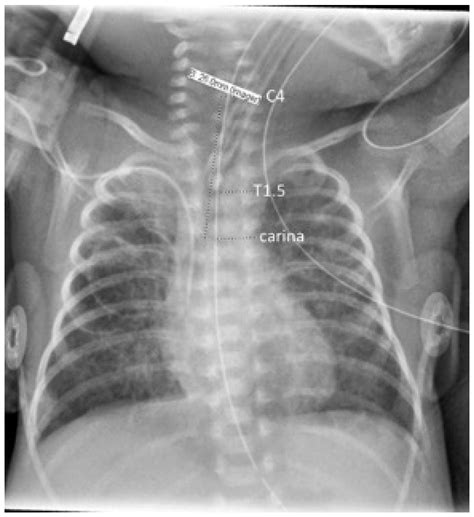

7. Verification: Verify correct tube placement using capnography, auscultation, and chest X-ray if necessary.